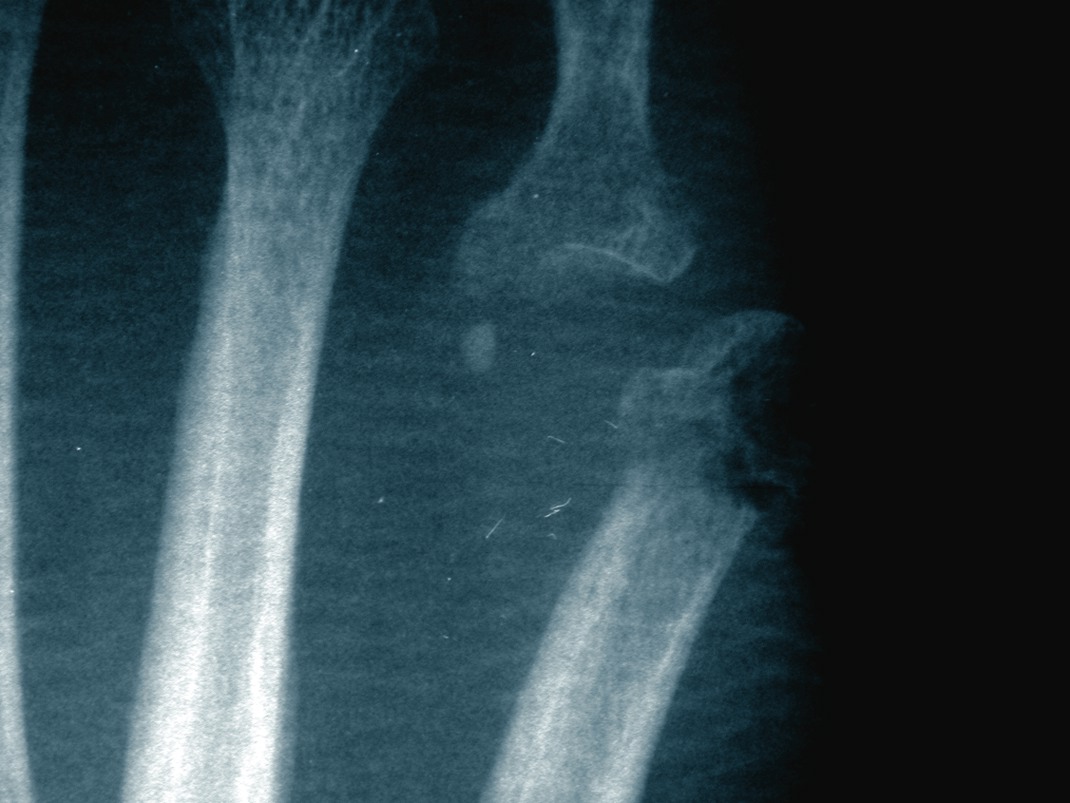

Study: MRI Can Change Ankle Pain Diagnosis

By Brian McCurdy, Senior Editor Can the use of magnetic resonance imaging (MRI) provide valuable insight into ankle injuries? A recent study in the American Journal of Roentgenology says MRI can potentially change diagnoses in patients with ankle injuries and possibly lead to less invasive treatments. Researchers studied 91 patients who were referred from one orthopedic foot and ankle surgeon for ankle MRI. The study concluded that MRI findings changed the management plans for 35 percent of patients in the study. For 32 percent of patients for whom management plans changed, practitioners formulated a less invasive plan, according to the study. The surgeon from whom patients were referred believed that in 66 percent of cases overall, the understanding of the patient’s condition had either depended on the MRI or had been improved by the imaging. Babak Baravarian, DPM, uses MRI studies “a great deal” when treating ankle pain. He says in cases of instability, there are frequent secondary findings like synovitis, osteochondral lesions or peroneal tendon injuries. “With good readings, a great deal of information is gained from an MRI study,” says Dr. Baravarian, the Co-Director of the Foot and Ankle Institute of Santa Monica. “I think the info is essential prior to most surgical cases about the ankle.” Lawrence A. DiDomenico, DPM says as costs decrease, it is easier to use the technology from an insurance standpoint. Increasing MRI use is becoming a more common and accepted practice pattern for musculoskeletal physicians. In the ‘80s, he recalls there was not much literature on specific soft tissue pathologies such as plantar fascia ruptures or peroneal tendon injuries. Dr. DiDomenico, an Adjunct Professor with the Ohio College of Podiatric Medicine, says MRI has made these conditions easier to diagnose, resulting in a recent increase in the reports in the literature. He adds that DPMs now see these pathologies more frequently. “It gives a much more accurate diagnosis and therefore, more focused treatment options for patients,” he says. Dr. DiDomenico says a facility without a well-trained musculoskeletal radiologist and/or MRI technologist may generate a poor reading (i.e., a one- or two-sentence report). Alternatively, more experienced staff will provide a detailed one- or two-page report, according to Dr. DiDomenico, the Director of the Reconstructive Rearfoot and Ankle Surgical Fellowship with the Ankle and Foot Care Centers in Youngstown, Ohio.